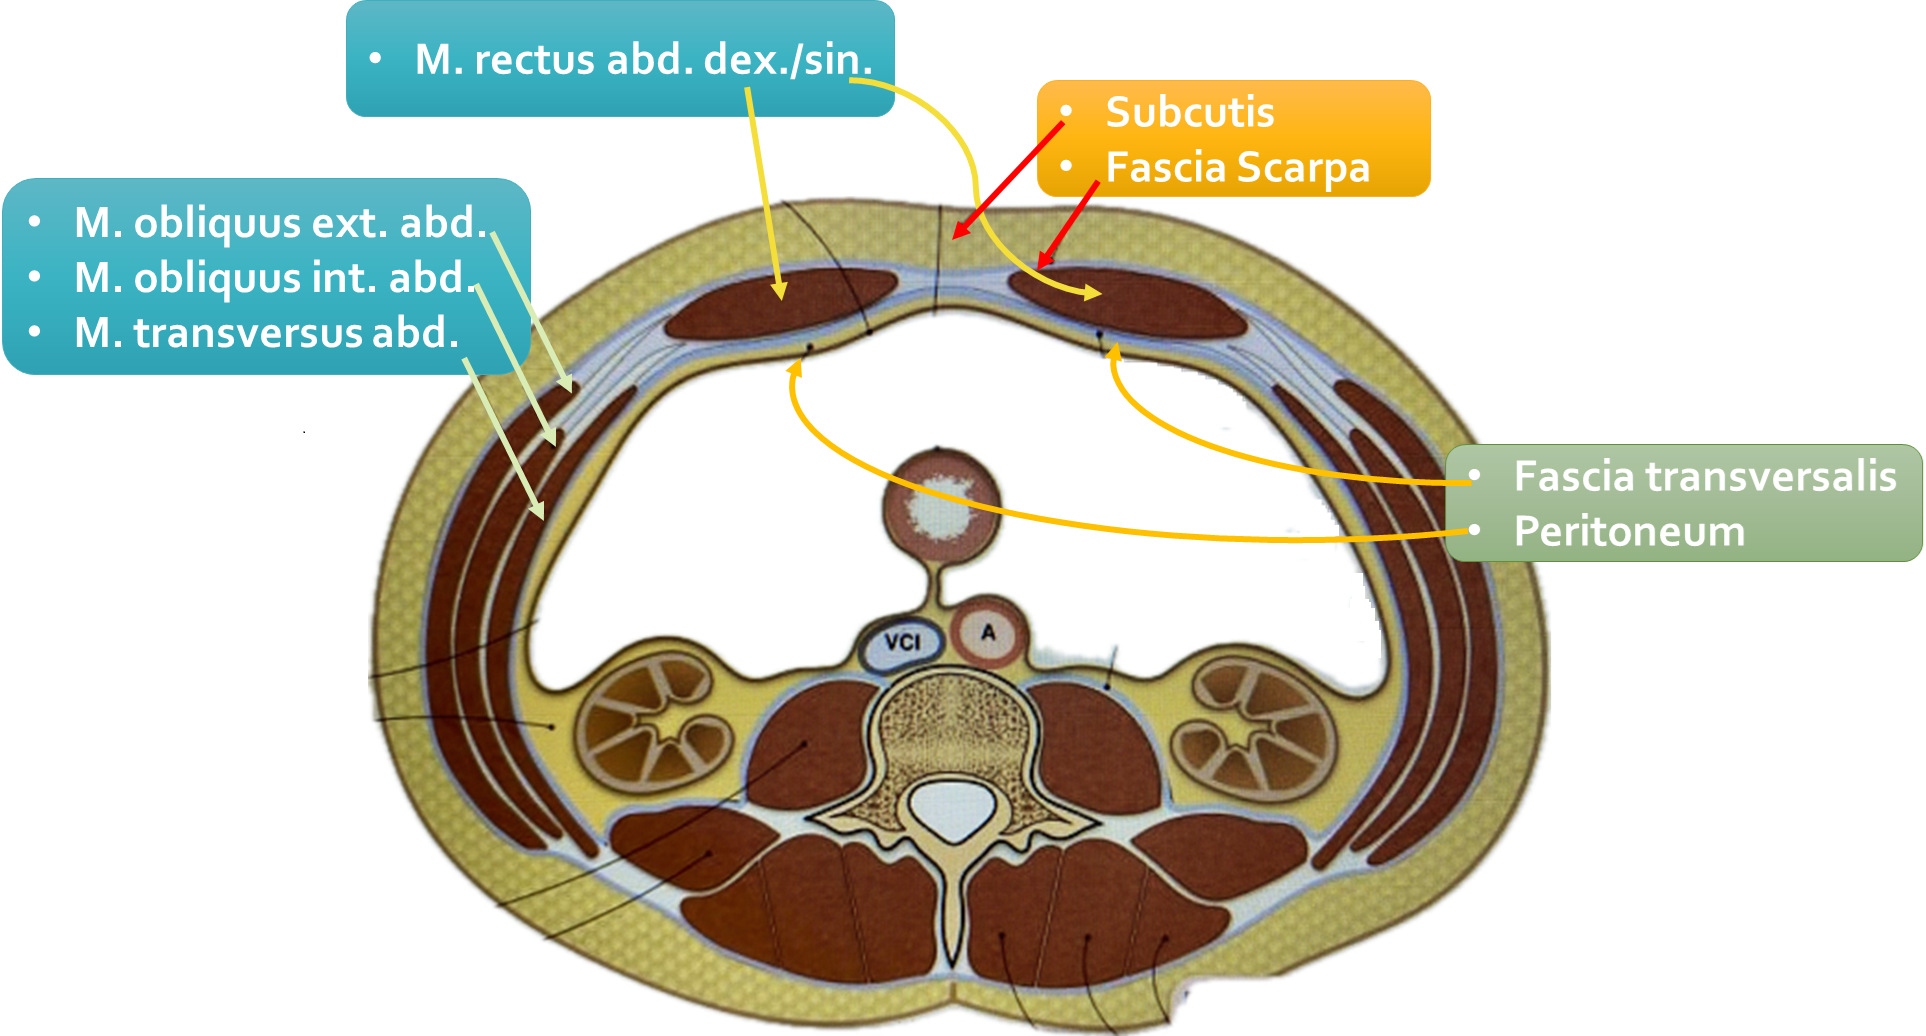

Donderdagavond, heb ik een Refreshment gehouden in het Medisch Centrum Leeuwarden. Onderwerp was de buikwand waarin we alle mogelijke herniaties belicht hebben. Daarnaast hebben we ook stil gestaan bij andere pathologie van de buikwand. Middels anatomie en een live-demo is de onderzoeksmethode van de buikwand gepresenteerd en hebben we vervolgens geoefend in een hands-on sessie. Leuk om met collega’s uit verschillende ziekenhuizen bezig te zijn en alles rondom dit onderwerp op te frissen.